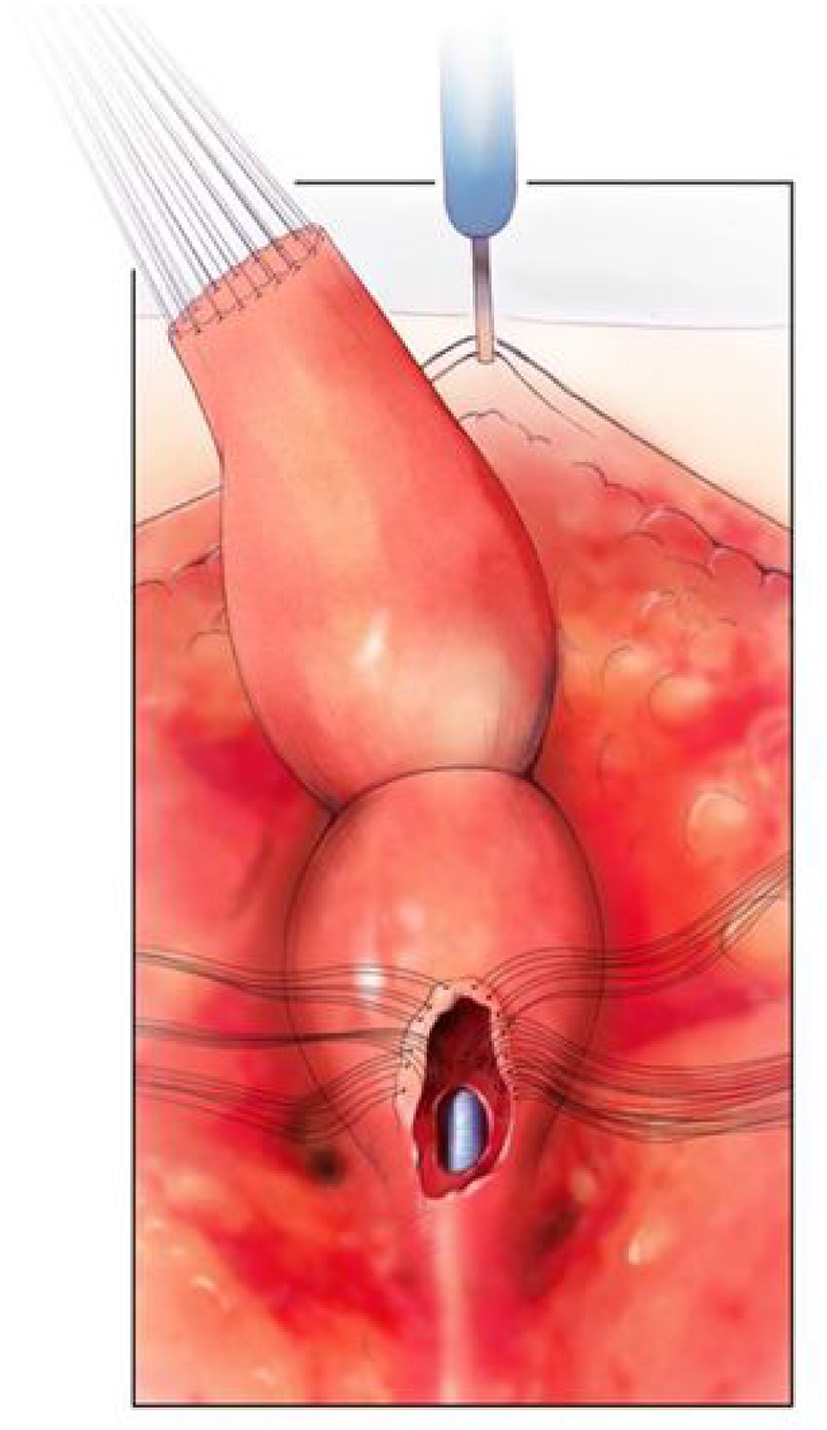

(3) Patients requiring a urogenital separation require more challenging reconstructive techniques. Identifying these patients up front may facilitate referral to high volume centers as required. Except in cases of very long common channels (with all three structures above the PC line), we would advocate starting with a posterior sagittal approach. The incision runs from the coccyx to just posterior to the common channel. Where possible the common channel should be left intact at the perineal level (Figure 3). The wound is widely opened and the surgeon's understanding of whether the rectum and vagina/s lie above or below the levators (PC line) is important. If present in the posterior sagittal field the rectum should identified and mobilized as previously described above. The rectal attachment to the vagina/s or common channel needs to be identified, confirming what was seen on preoperative imaging, and divided. If the connection is to the common channel, care must be taken not to injure or narrow the common channel. At this stage the posterior vagina is opened close to where it joins the common channel (urethro-vaginal fistula). Sutures are placed on the edges of the vagina/s and the surgeon is able to look inside and identify the connection between the vagina/s and the common channel and urethra (Figure 4). The next stage is to start the separation of the vagina/s from the common channel, urethra, and bladder neck. This is done in the same way as is performed in a male undergoing a PSARP for a recto-urethral fistula, with lateral dissection done first, then anterior (Figure 5). Once the bladder neck is reached or the dissection becomes too high, the surgery should be continued in a trans-abdominal fashion. This will prevent placing the ureters in danger of being injured. If the ureters are ectopic they can be stented cystoscopically at the start of the procedure.

FIGURE 3

www.frontiersin.org

Figure 3. The posterior sagittal view with the rectum, vagina, and common channel dissected out but not opened. Reproduced with permission from © Center for Colorectal and Pelvic Reconstruction at Nationwide Childrens Hospital.